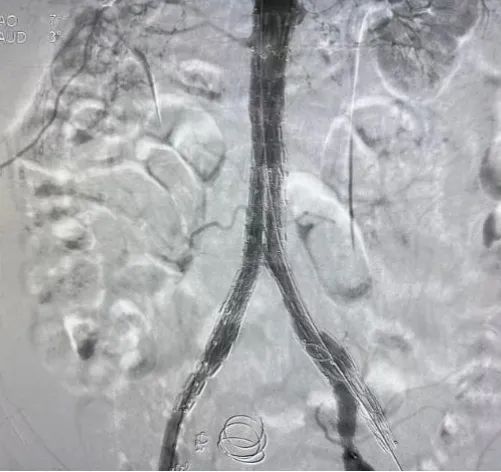

术前DSA造影